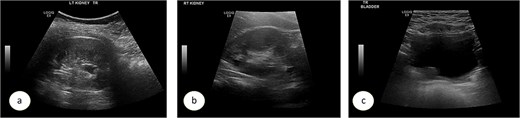

A 7-year-old child was referred to the pediatric urology clinic due to a history of recurrent febrile urinary tract infections and urge incontinence, accompanied by constipation (Bristol 2). These symptoms persisted despite meticulous conservative management, including urotherapy. Ultrasound (US) revealed bilateral pelviectasis and voiding cystourethrogram (VCUG) revealed bilateral Grade 3 VUR and a mildly trabeculated bladder wall, whereas the urethra appeared normal (Fig. 1a–d). A DMSA renal scan verified bilateral renal scarring, revealing differential renal function of 40% in the right kidney and 60% in the left kidney (Fig. 1e). Endoscopic intervention was warranted, and 1 ml of Deflux was injected on the left side and 0.6 ml on the right side, successfully creating an adequate mound. The patient was discharged in stable condition for several hours following surgery, despite being anuric. Subsequently, the patient experienced intense abdominal pain and was admitted to the emergency department. The physical examination was uneventful, except for moderate hypertension. The urinalysis revealed microscopic hematuria. His urea level was 16 mmol/L, and creatinine rose to 126 umol/L from a baseline of 40 umol/L. Post operative US at emergency room demonstrated increased bilateral hydronephrosis (Fig. 2).

Post Deflux injection ultrasound images showing the left (a), and right (b) kidneys and the urinary bladder (c).